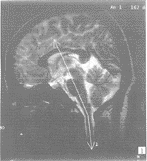

发育正常、没有中枢神经系统症状及体征的成年人100例,男50例,女50例,平均年龄38周岁(18~55周岁)。经临床+普通X线摄影诊断为颅底凹陷症患者6例,男1例,女5例,平均年龄43岁。病因:发育性5例,外伤性1例。所有病例均行MR扫描,扫描时注意头部保持自然、舒适体位,避免过度屈伸。扫描仪器采用岛津1.0T(SMT-100X)超导型MR设备。头线圈。所有检查均行矢状位T2W扫描(TR1800/TE80)。采用正中矢状层面,沿脑桥-延髓轴线,以及上颈髓(颈1~3)轴线进行角度测量(图1)。

图1 矢状位T2W扫描(TR1800/TE80),洞脑桥-延髓轴线,以及上颈髓(颈1~3)轴线进

行自然角度测量